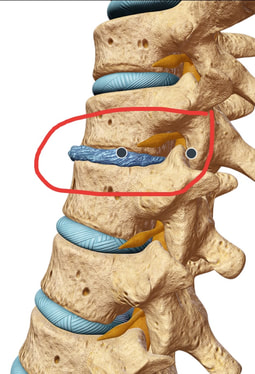

In some people this degenerative process is not associated with pain, while in others degenerative disc disease can cause neck and back pain, stiffness, and soreness. Degenerative discs can rupture, leading to arm or leg pain if the disc pinches nerves. The process of degeneration causes discs to gradually lose height, form spurs, and cause narrowing around the nerves, which can also lead to arm and leg pain